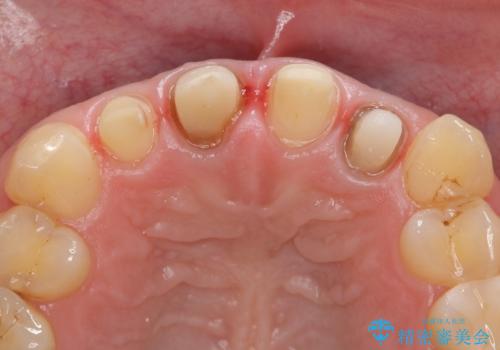

- 前歯の色や長さ、歯茎との隙間の金属が気になるのでセラミックで治療したいといらっしゃった方の症例です。

見た目改善のため、前歯4本をオールセラミッククラウン(スペシャル)で補綴しました。

右上1と左上2は再根管治療を行っております。